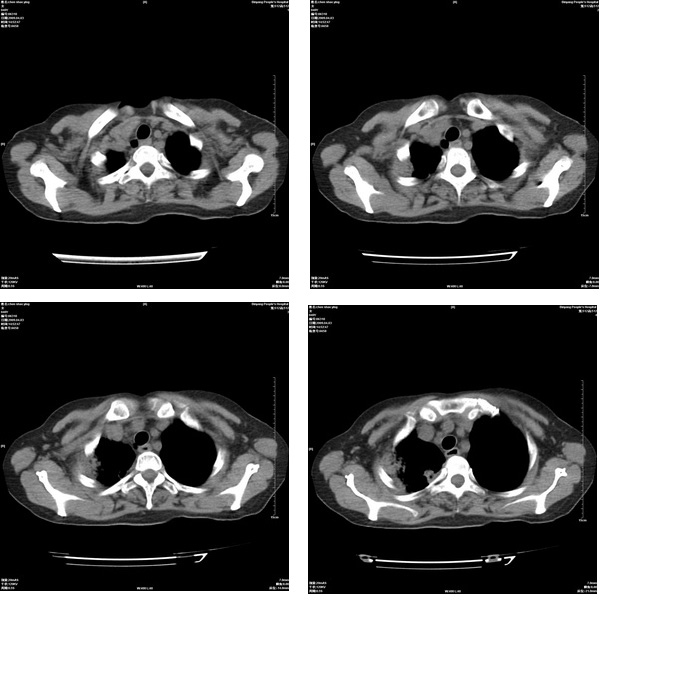

患者,女,48岁,发热伴陈发性咳嗽5天,偶尔痰中带血。体温约38°~40°;白细胞明显减低0.85x10的9次方/升。入院后抗炎、抗痨一周复查病灶明显进展。

右上肺后段实变影,内见支气管气象,肺门未见软组织肿块,气管前方有肿大淋巴结。左下肺见多个类圆形结节影。考虑:1.右上肺后段大叶性肺炎,需进一步检查病原体种类,应多询问病史,条件许可考虑做纤支镜检查2.左下肺结节影性质待定

考虑右上肺后段大叶性肺炎不除外结核,伴双肺结节播散灶,希定期复查。